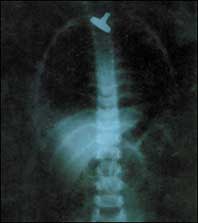

إطالة الأطراف وإصلاح تشوهات العظام بطريقة اليزاروف!

إن الإعاقة الناجمة عن قصر أحد الطرفين السفليين أو التشوهات العديدة الخلقية والمكتسبة في الأطراف السفلية و العلوية كانت دائماً الشغل الشاغل للأطباء لإي.........